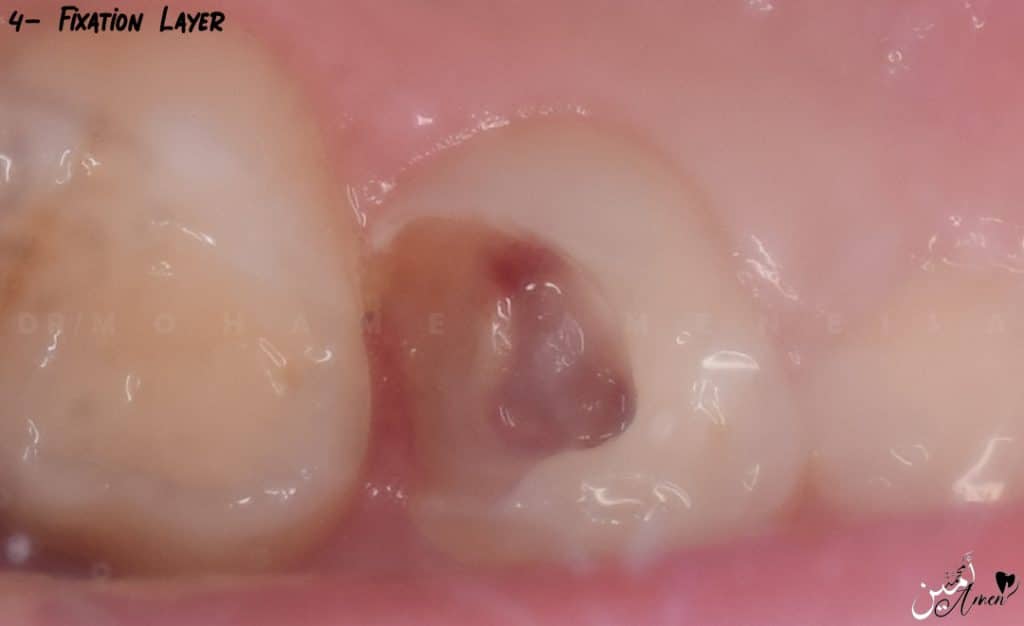

Here, instead of using formocresol, you can use ferric sulfate or sodium hypochlorite, and the easiest and cheapest one is sodium hypochlorite.

- You take a piece of cotton and soak it in sodium hypochlorite and put it in the cavity for 30 seconds, Here you have preserved the radicular pulp vitality, and it will give you the fixation you want without the harm of formocresol

I will remind you that you do these steps after you are 100% sure that the bleeding has stopped.